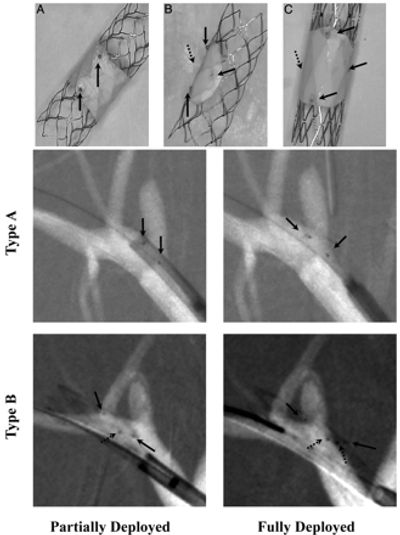

One approach to treat intracranial aneurysms is to use stent-like flow diverters to create thrombogenesis conditions in the aneurysm with minimal sack manipulation. Ninety percent of IA’s occur at a bifurcation, potentially in the vicinity of smaller branches. Therefore, the devices need to be flexible for easy deliverability and porous enough to avoid adjacent arterial branches occlusion, which could cause additional strokes. One of the simple Uniform Flow Diverters (UFD) being used in restricted human cases, while effective in some sidewall IA’s, is inappropriate for usage with bifurcation aneurysms. We have been heavily involved in a research projects to investigate, develop and optimize the design of a new Asymmetric Flow Diverter (AFD), for treatment of bifurcation IA’s without the short-comings associated with current uniform flow diverting stents. The new device would consist of a low-porosity region which will cover only the aneurysm neck, to effectively divert the flow. The rest of the device will be high-porosity to reduce the chance of blockage of adjacent arteries. We treated in-vitro and in-vivo bifurcation IA’s models using the new AFDs, and studied the flow changes in the aneurysm dome and in the adjacent branches.

Left/above photo: A−C, Self-expanding Asymmetric Flow Diverter devices. Upper: Photographs of the 3 types of these stents. Lower: Angiograms showing deployment of types A and B. Type A contains a sleeve (PTFE patch) approximately 4–5 mm wide covering the central part of the stent; types B and C have a patch covering only a given stent region. Types A and B have a closed-cell structure, whereas type C has an open-cell structure. In the photographs, black arrows indicate the platinum markers used to guide the stents during the procedure and dotted arrows indicate the marker position not visible in photographs.